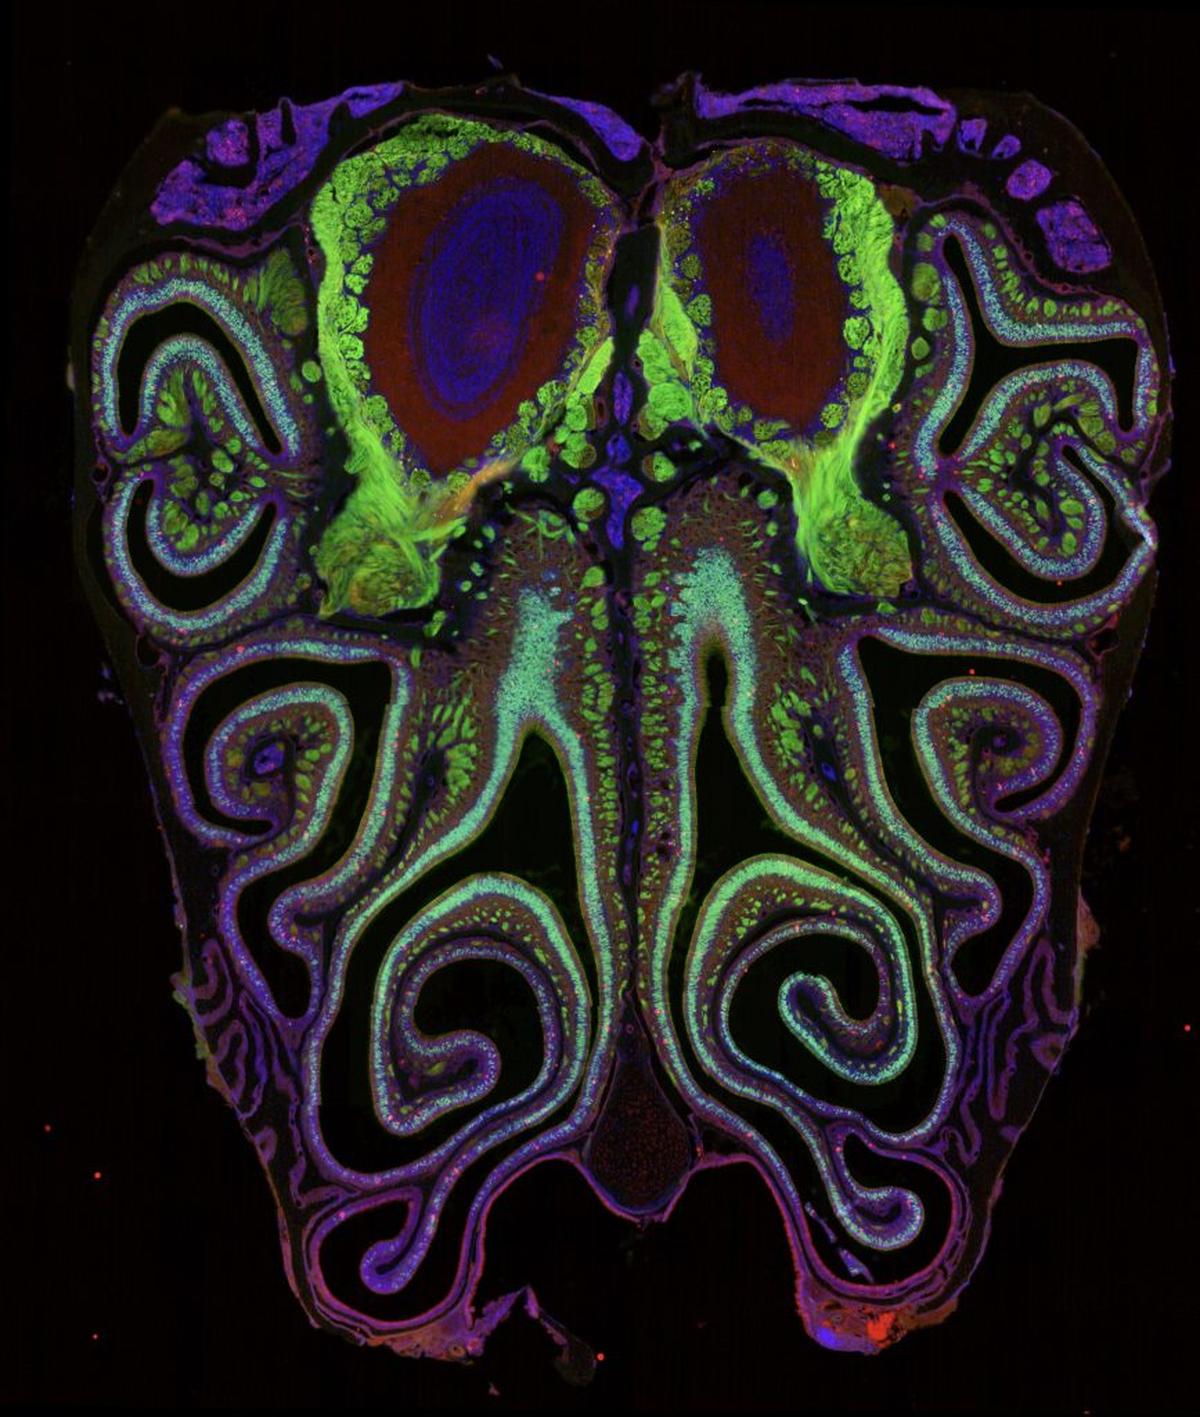

A microscope photo of a cross section of a mouse nose. The mouse was genetically modified to express green fluorescent protein in smell neurons. A small subset of dying neurons is labeled in red. (Datta Lab via SWNS)

Working in mice, study senior author Datta and his team have now created the first detailed map of how the thousand-plus types of smell receptors in the nose are organized.

They discovered that unlike what researchers had previously believed, the neurons expressing the receptors have a high degree of spatial organization: they form horizontal stripes based on receptor type from the top of the nose to the bottom.

The team discovered that the neurons are organized into tight, overlapping, horizontal stripes from the top of the nose to the bottom based on the type of smell receptor they express.

They said the highly organized receptor map was consistent across the mice and mirrored the organization of smell maps in the brain, just like researchers have observed in vision, hearing, and touch.